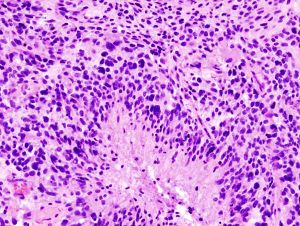

قد يتم إجراء خزعة باستخدام إبرة بالتوضيع التجسيمي للأورام الدبقية في المناطق التي يصعب الوصول إليها أو المناطق الحساسة جدًا داخل الدماغ التي قد تتضرر من أي عملية أكثر توسعًا. خلال خزعة إبرة التوضيع التجسيمي، يحفر جراح الأعصاب ثقبًا صغيرًا في الجمجمة. ثم يتم إدخال إبرة رفيعة من خلال ثقب. تتم إزالة الأنسجة من خلال الإبرة، والتي كثيرًا ما يتم توجيهها باستخدام التصوير المقطعي المحوسب أو المسح الضوئي بالتصوير بالرنين المغناطيسي. ثم يتم تحليل عينة الخزعة تحت المجهر لتحديد ما إذا كانت سرطانية أو حميدة.

تعد الخزعة هي الطريقة الوحيدة لتشخيص ورم الدماغ بشكل نهائي وإمدادك بتشخيص لتوجيه قرارات العلاج. واستنادًا إلى هذه المعلومات، يمكن لطبيب الأمراض تحديد درجة الورم في الدماغ أو مرحلته.

وتنقسم الأورام إلى أربع درجات حيث تكون أورام الدرجة الأولى الأبطأ نموًا وأكثرها خلايا حميدة وتحتوي أورام الدرجة الرابعة على أكثر الخلايا السرطانية شذوذًا وعنفًا.